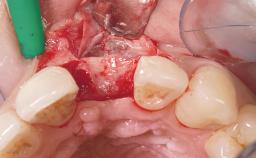

Late Flapless Placement of an Implant in a Maxillary Left Central Incisor Site

A 39-year-old male patient presented with a chief complaint of discomfort and gingival discoloration around his maxillary left central incisor. He was in good general health and was a non-smoker. His past dental history was significant because of the traumatic fracture of tooth 21 in a sporting accident at age 13. Initial dental treatment included endodontic therapy and a full-coverage restoration. The patient became symptomatic 5 years later, when structural failure of the tooth resulted in the dislodgment of the crown. Endodontic retreatment, apical surgery, and post-and-core restoration were performed.

Bone Augmentation Horizontal|Staged

Soft Tissue Grafting Simultaneous

Bone Volume Deficient horizontally, requiring prior grafting